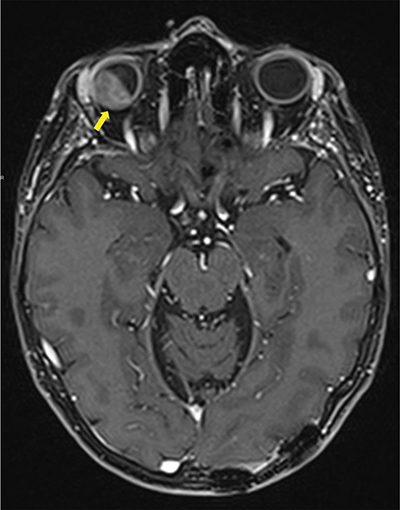

Figure 1

Contrast enhanced Axial T1 Dixon MRI-scan showing intra-orbital metastasis (arrow) invading all layers of the eyeball and the intra-conal fat.